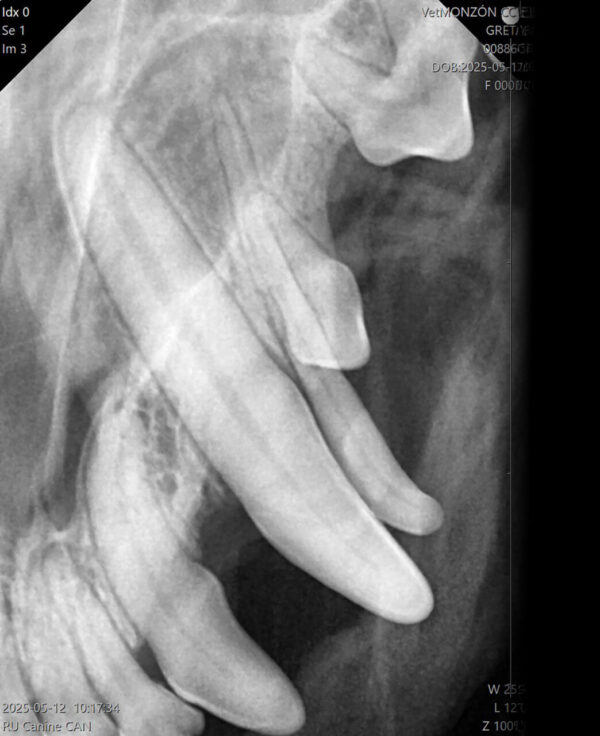

Cuando en una exploración visual de la boca observamos una ausencia dental debemos hacer una radiografía que nos indique la causa, que puede ser de origen genético o deberse a alteraciones sufridas durante las primeras etapas del desarrollo dental o a lo largo de la vida del animal.

A nivel radiológico nos podemos encontrar con varias situaciones:

- Ausencia del diente porque no se ha formado (agenesia).

- El diente no ha erupcionado por estar ectópico (fuera de su área anatómica).

- El diente está incluido o impactado (cuando no logra erupcionar o lo hace parcialmente por diferentes causas).

También puede ser debida a la pérdida dental (por EP, por ejemplo) o a fracturas de corona en las que quedan restos de estructuras dentales bajo la encía. Por tanto, dependiendo de ello, decidiremos el enfoque terapéutico que tomaremos en cada paciente con ausencia dental. (imágenes 14-17).

Aumento del número de dientes

La presencia de dientes supernumerarios también debe ser estudiada mediante la radiología intraoral. La causa principal es genética y la radiología nos permitirá valorar su naturaleza, si se trata de un diente definitivo o la falta de exfoliación de dientes deciduos (en caso de no tenerlo claro a la inspección visual). En este último caso, podremos valorar el estado de la raíz y su relación con el diente permanente, aspectos que debemos tener en cuenta a la hora de realizar su extracción (imágenes 18 y 19).

Las consecuencias pueden ser insignificantes en zonas de mínima intercuspidación, pero pueden ser causa de lesiones traumáticas o apiñamiento que disminuyan los mecanismos fisiológicos de autolimpieza.